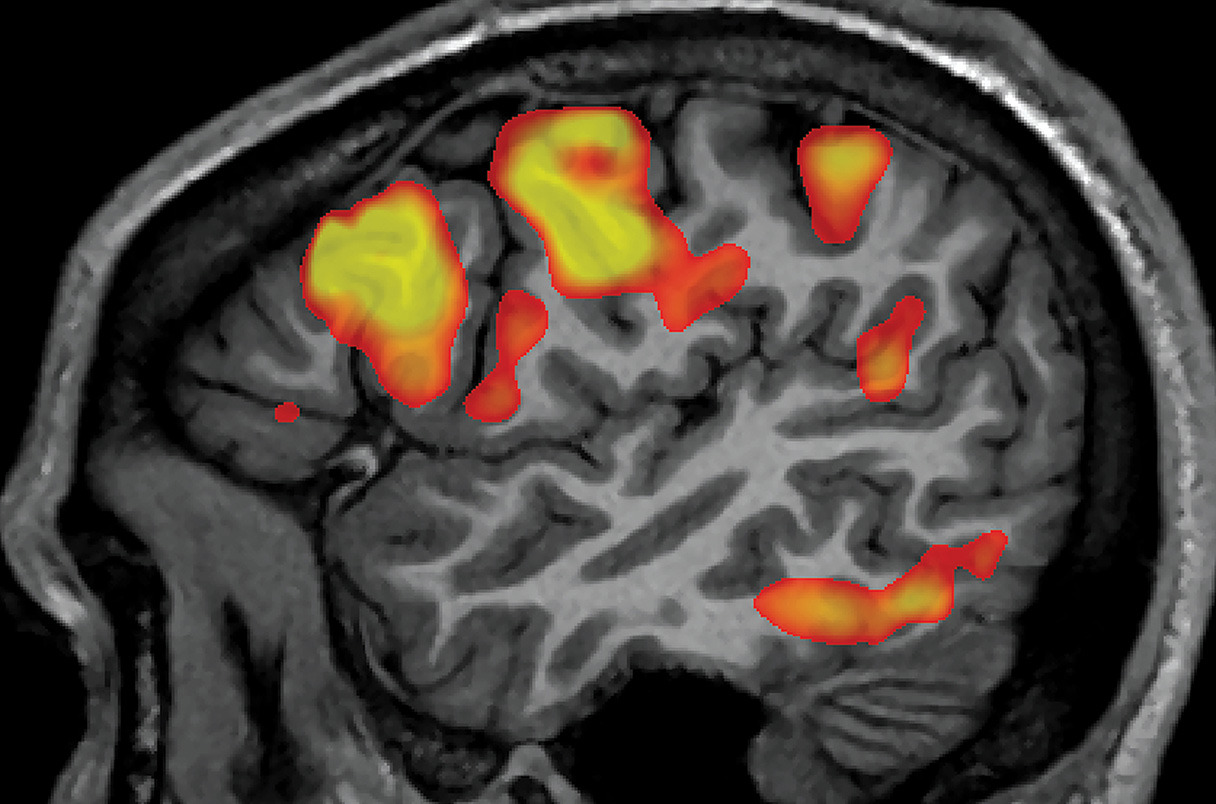

- 참가자들에게 짧은 영상(물체, 장면, 행동 등을 담은)을 보여주며 기능적 자기공명영상(fMRI)(fMRI)으로 뇌 활동을 스캔. Medical Xpress+1

- 스캔된 뇌 신호 데이터를 AI 모델이 해독해, 그 사람이 보고 느낀 내용을 텍스트 문장으로 생성하는 방식. Medical Xpress